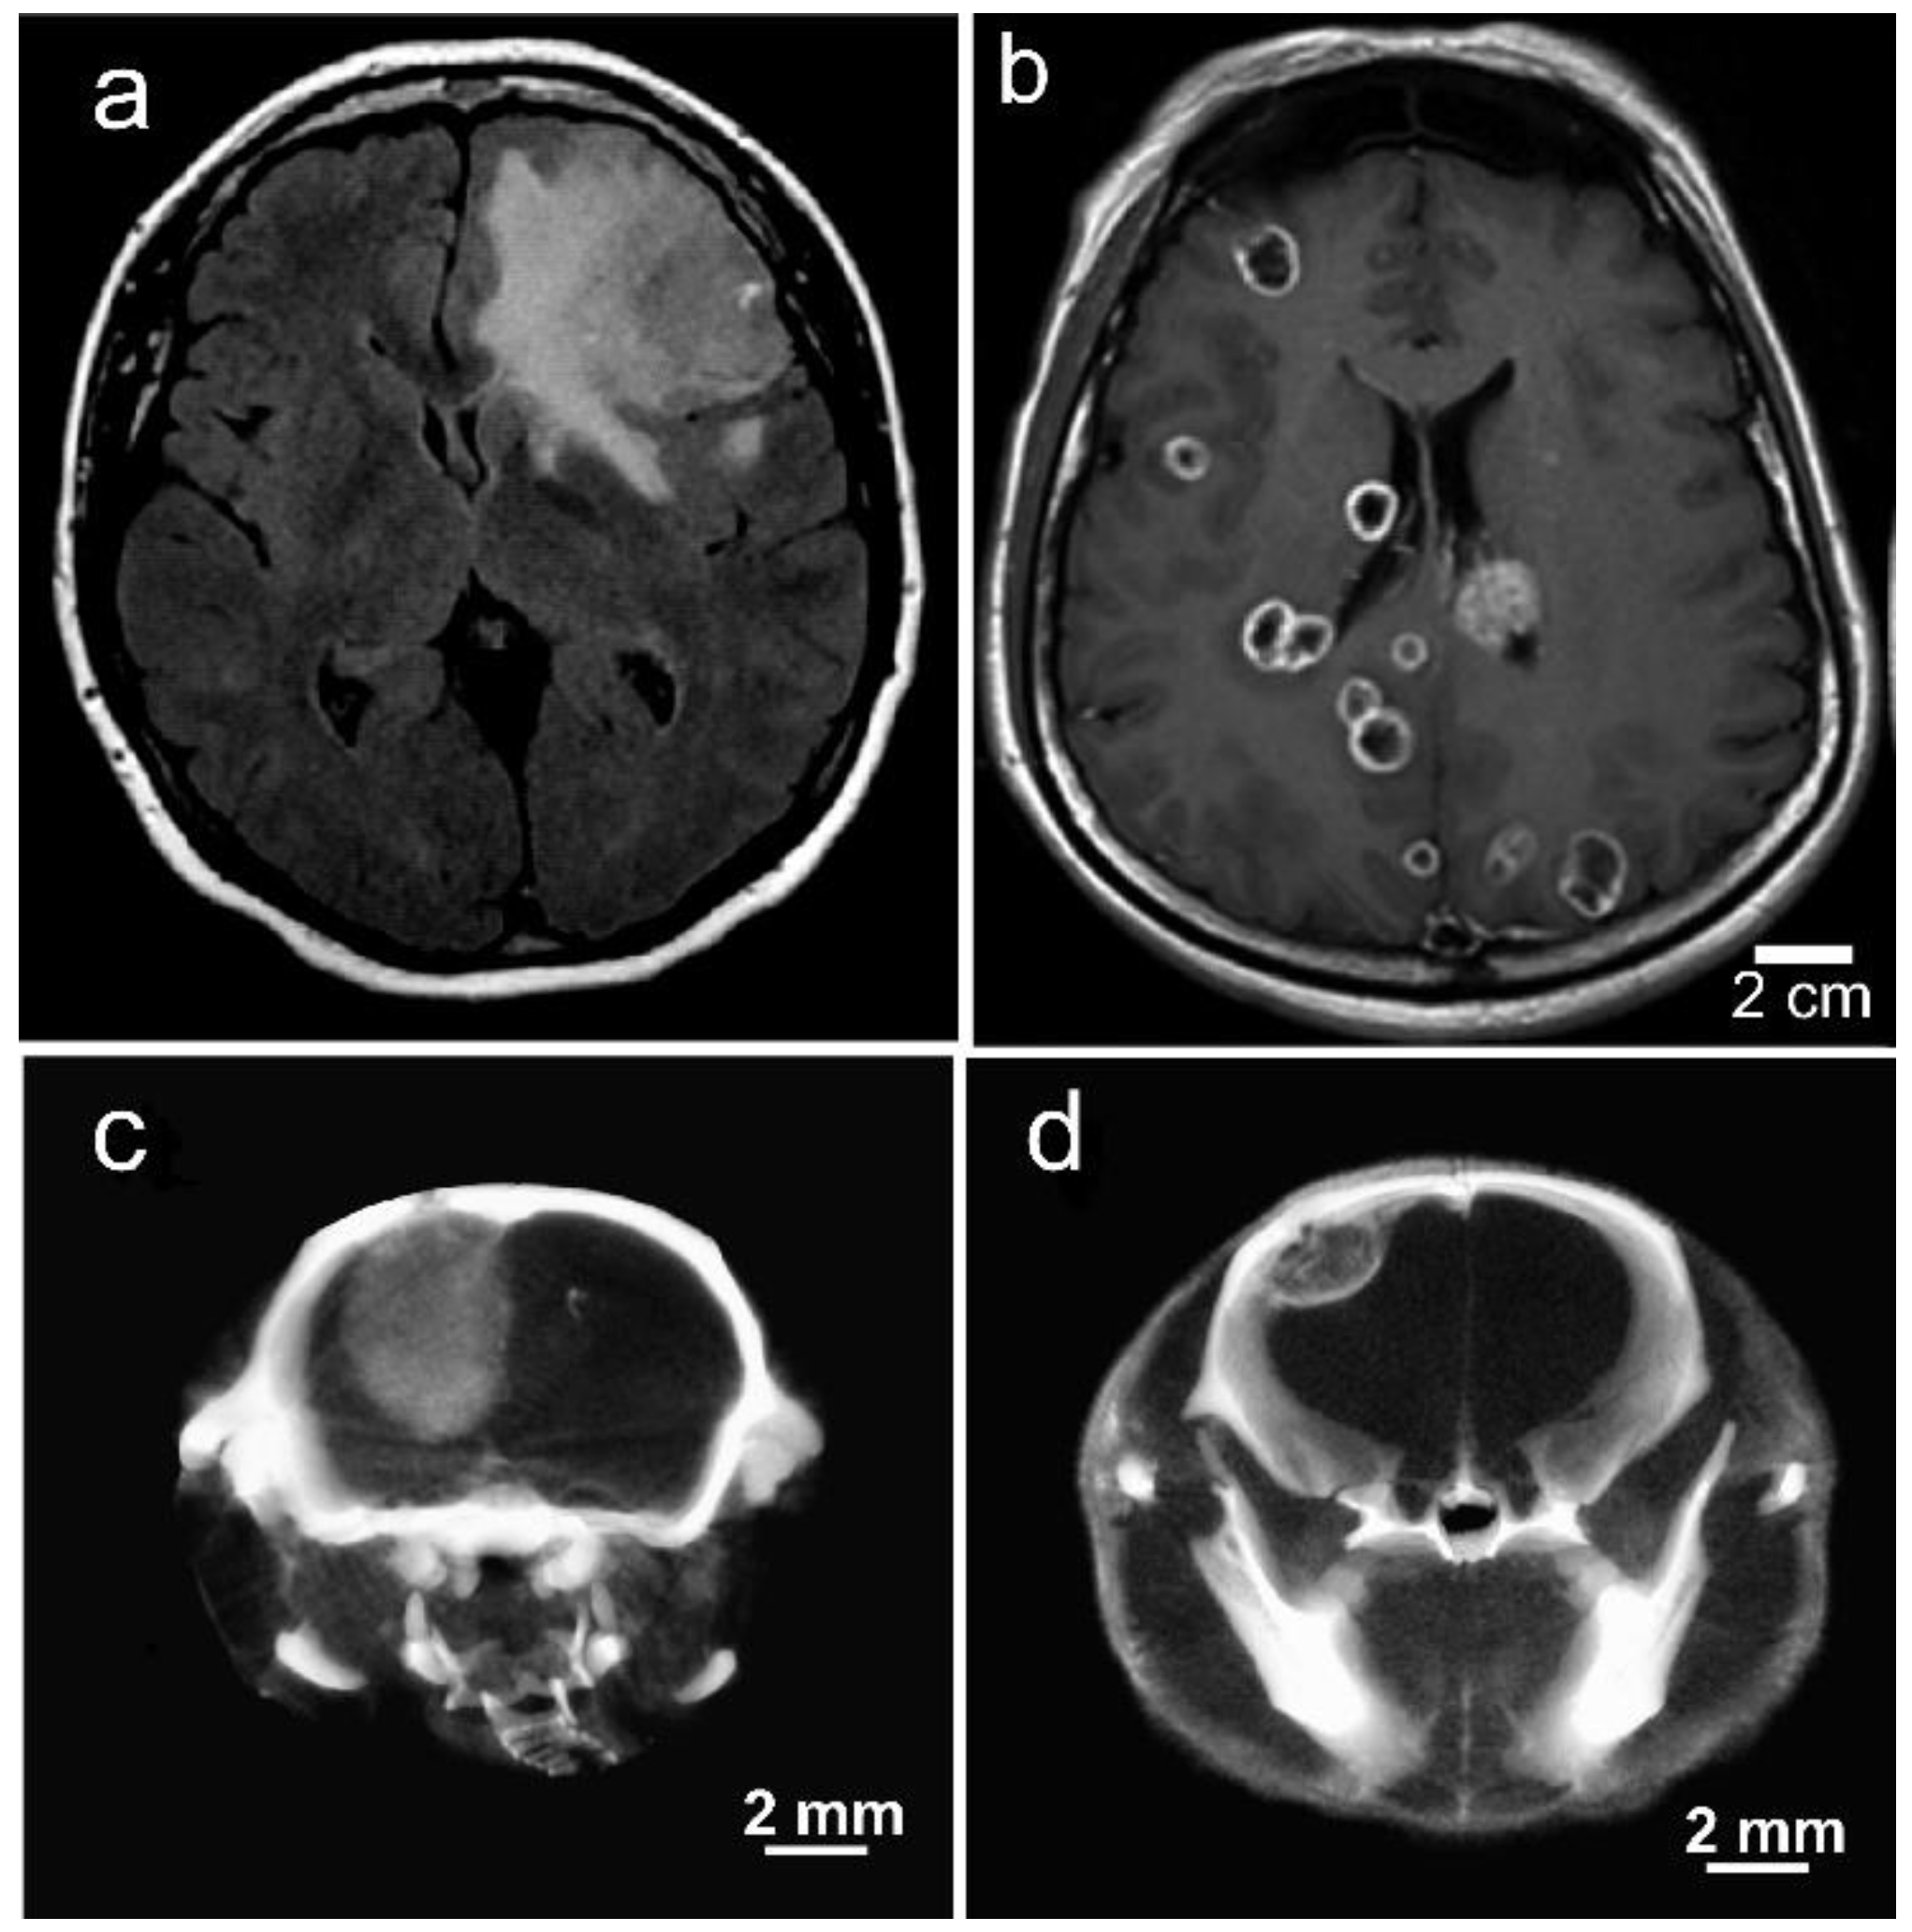

1.8. Iodine-Enhanced Radiotherapy of Brain Metastases

1.9. Iodine Nanoparticle Targeting to Brain Metastases